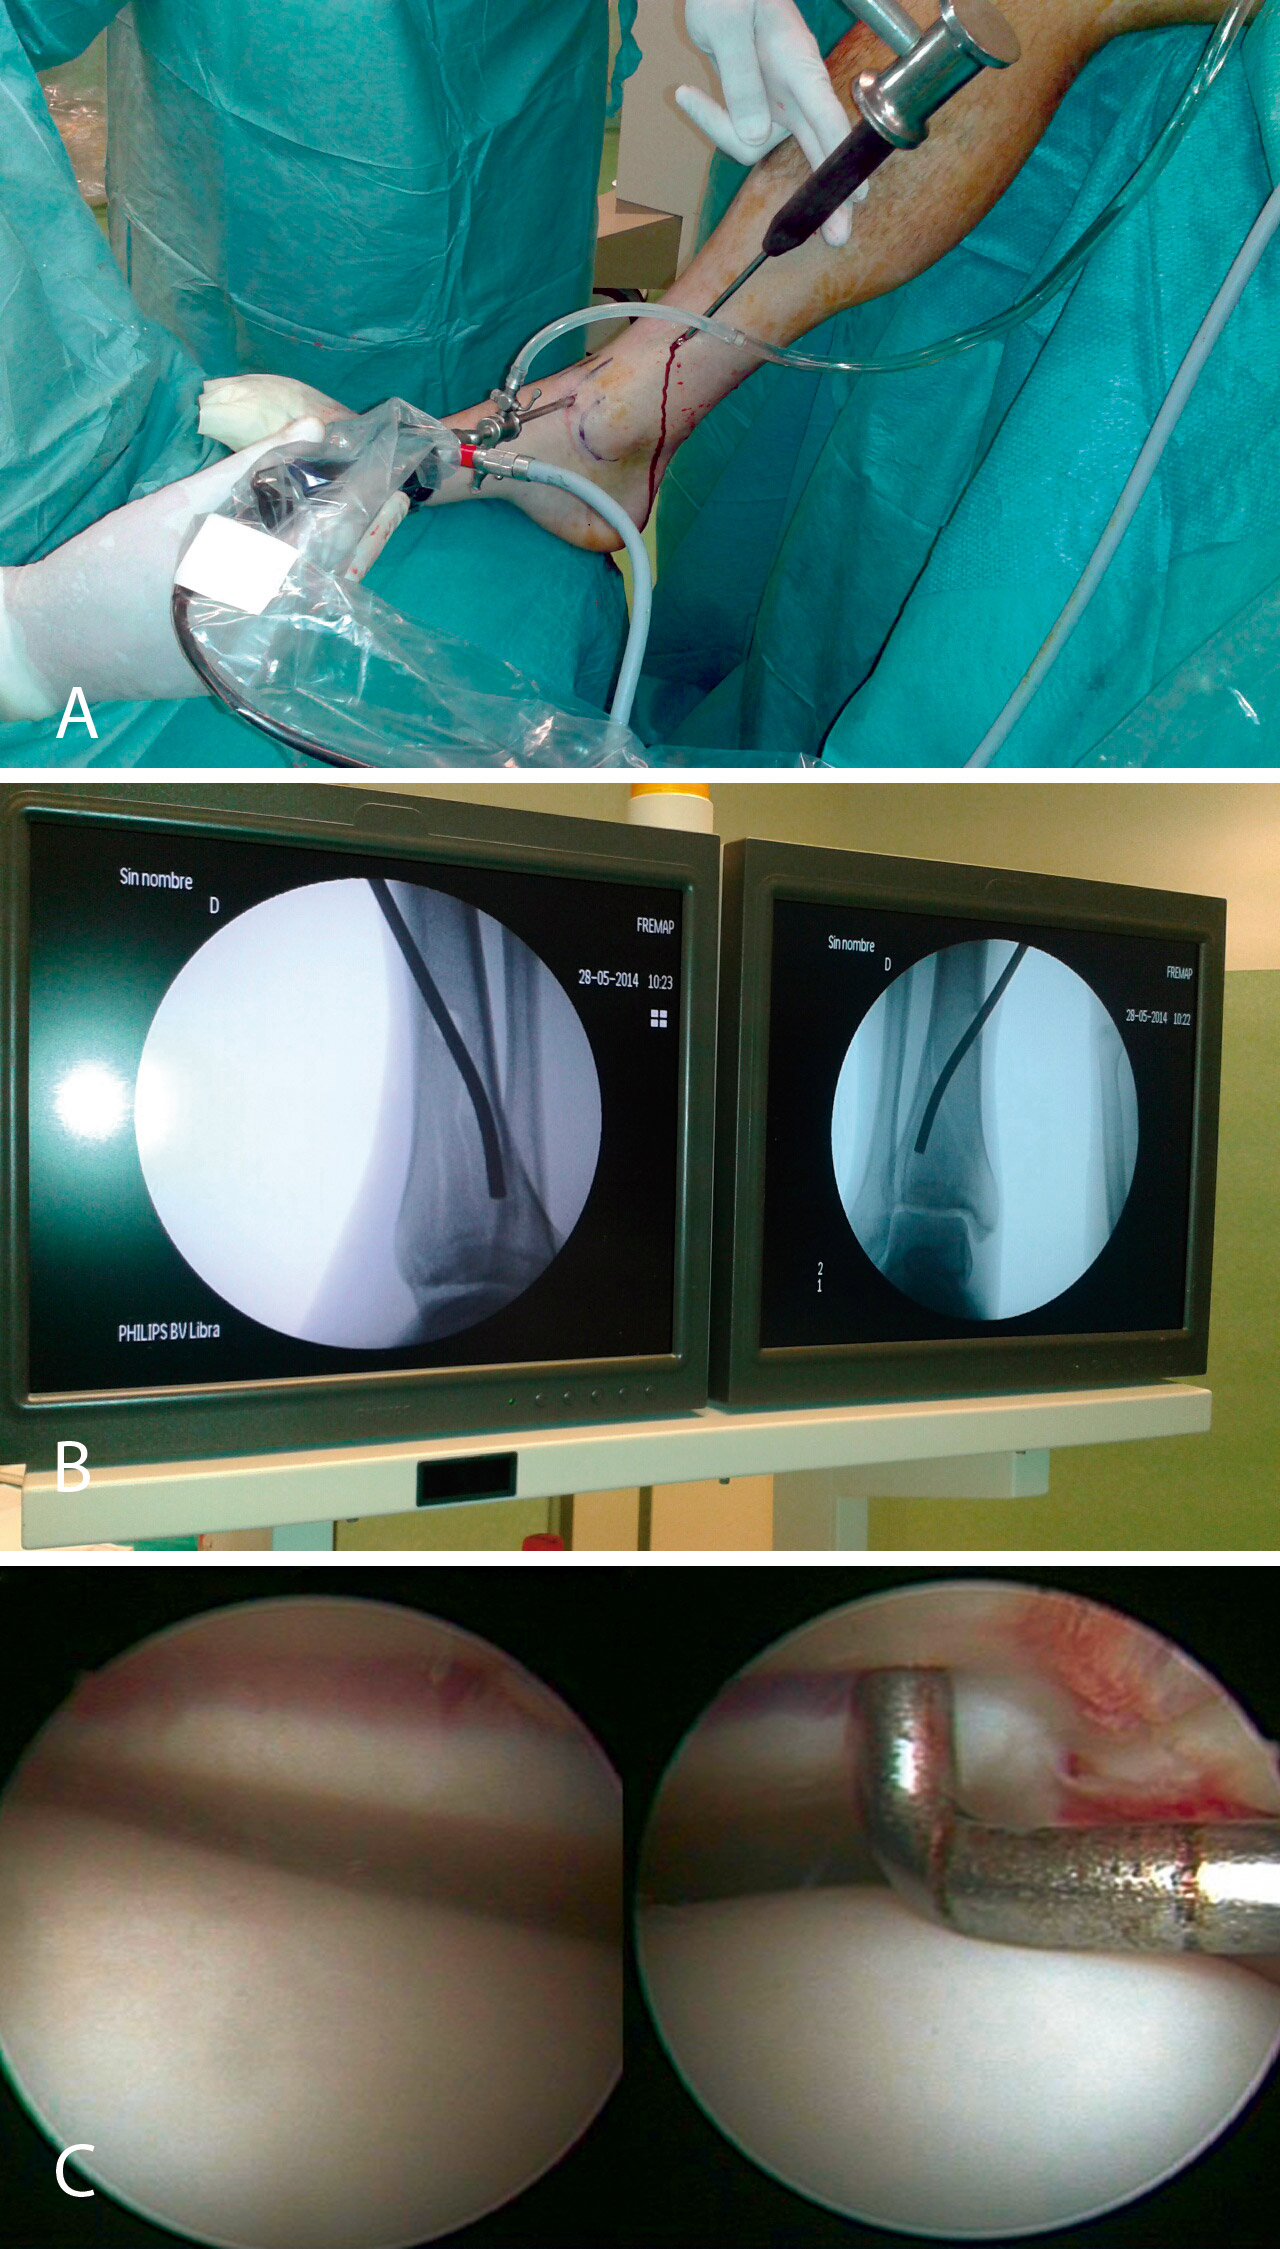

1. Una fractura B2, fractura-depresión (split fracture) donde colocaremos al paciente con la pierna en flexión en una posición similar a la de una artroscopia de rodilla, lo que nos facilita la colocación del impactor y la percusión del fragmento, mientras controlamos por artroscopia y radioscopia la reducción del mismo.

Comenzamos realizando el tiempo artroscópico por los portales habituales de la artroscopia de tobillo (anterointerno y anteroexterno), aunque hay que tener en cuenta que la posición de los fragmentos óseos puede modificar la altura de los mismos. En primer lugar, realizamos limpieza y desbridamiento articular del hemartros fracturario hasta distinguir el trazo de fractura.

Nos colocamos sentados frente al miembro lesionado, elevando la mesa quirúrgica con la pantalla de la torre de artroscopia frente a nosotros. Tras realizar los portales de artroscopia, procedemos a un lavado exhaustivo de la articulación dejando introducir el suero de la bolsa de artroscopia (no utilizamos bomba de presión) hasta que dejen de salir restos de hematoma por el aspirador de artroscopia. A continuación, introducimos el sinoviotomo y resecamos el hemartros fracturario hasta que identifiquemos los fragmentos del foco de fractura (Figuras 4 y 5).

Figura 4. Caso 1: fractura tipo B2 (fractura-depresión o split fracture). Posición del cirujano y del paciente; colocación del monitor de radioscopia y de artroscopia.

Figura 5. Lavado exhaustivo. Desbridamiento del hemartros y limpieza articular.

Posteriormente, realizamos un orificio en la cortical de la diáfisis de la tibia a cierta distancia del foco de fractura mediante una broca canulada de 8 mm que nos permita introducir un impactor curvo con el que percutir en el fragmento hundido hasta colocarlo a nivel de la superficie articular, controlando la reducción por artroscopia y radioscopia de manera simultánea.

Una vez reducida la fractura, fijamos los fragmentos de manera provisional con una o más agujas de Kirschner y las vamos sustituyendo por tornillos canulados de 4,5 mm. Cuando realizamos este procedimiento, ampliamos habitualmente un centímetro la herida de introducción del tornillo para poder colocar un pequeño separador que nos permita rechazar los elementos neurovasculares y tendinosos de la zona del tobillo.